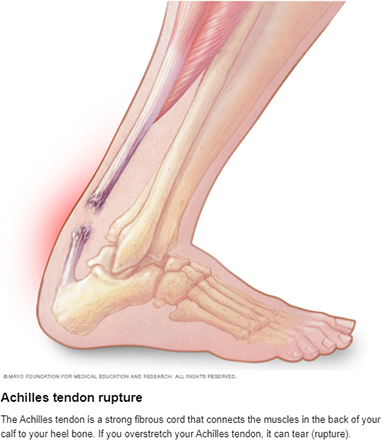

Achilles Tendon Rupture Faribault Mayo Clinic Health System

Achilles tendon pain Causes. when to see a doctor and treatment